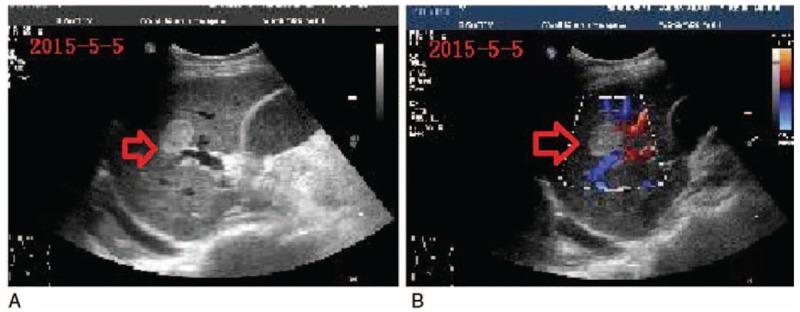

We report an extremely rare case with multiple masses which were identified in the head and body of the pancreas.

我们报告了一例极其罕见的病例,在胰腺头部和体部发现了多个肿块。